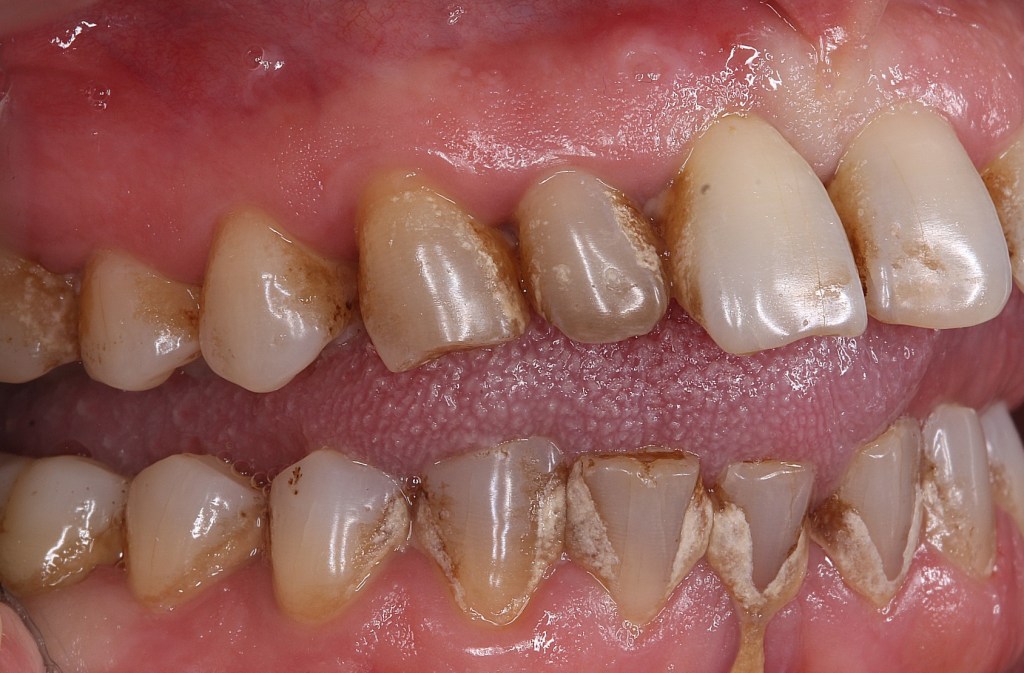

Atașez pozele unui pacient care până la vârsta de 44 ani nu a fost niciodată la dentist, cu reflex de vomă exagerat și igienă deficitară, speriat că i s-a propus extracția a peste 50% din dinți din cauza mobilității generalizate de gradul II și III. Am mers pe varianta clasică, debridare parodontală nechirurgicală, la microscop, cu anestezie locala în toate cadranele, realizată într-o singură ședință. Am administrat antibiotic pe cale generală și am urmărit respectarea indicațiilor de igienă prin controale lunare. Rezultatele la 6 luni vorbesc de la sine, acum putând să ne ocupam liniștiți de regenerarea defectelor osoase de la nivelul 21 22, de altfel singurii dinți care mai au mobilitate.

Iar retracția de la 31 s-a vindecat singură 🙂 Pentru că timpul e, uneori, cel mai bun tratament.